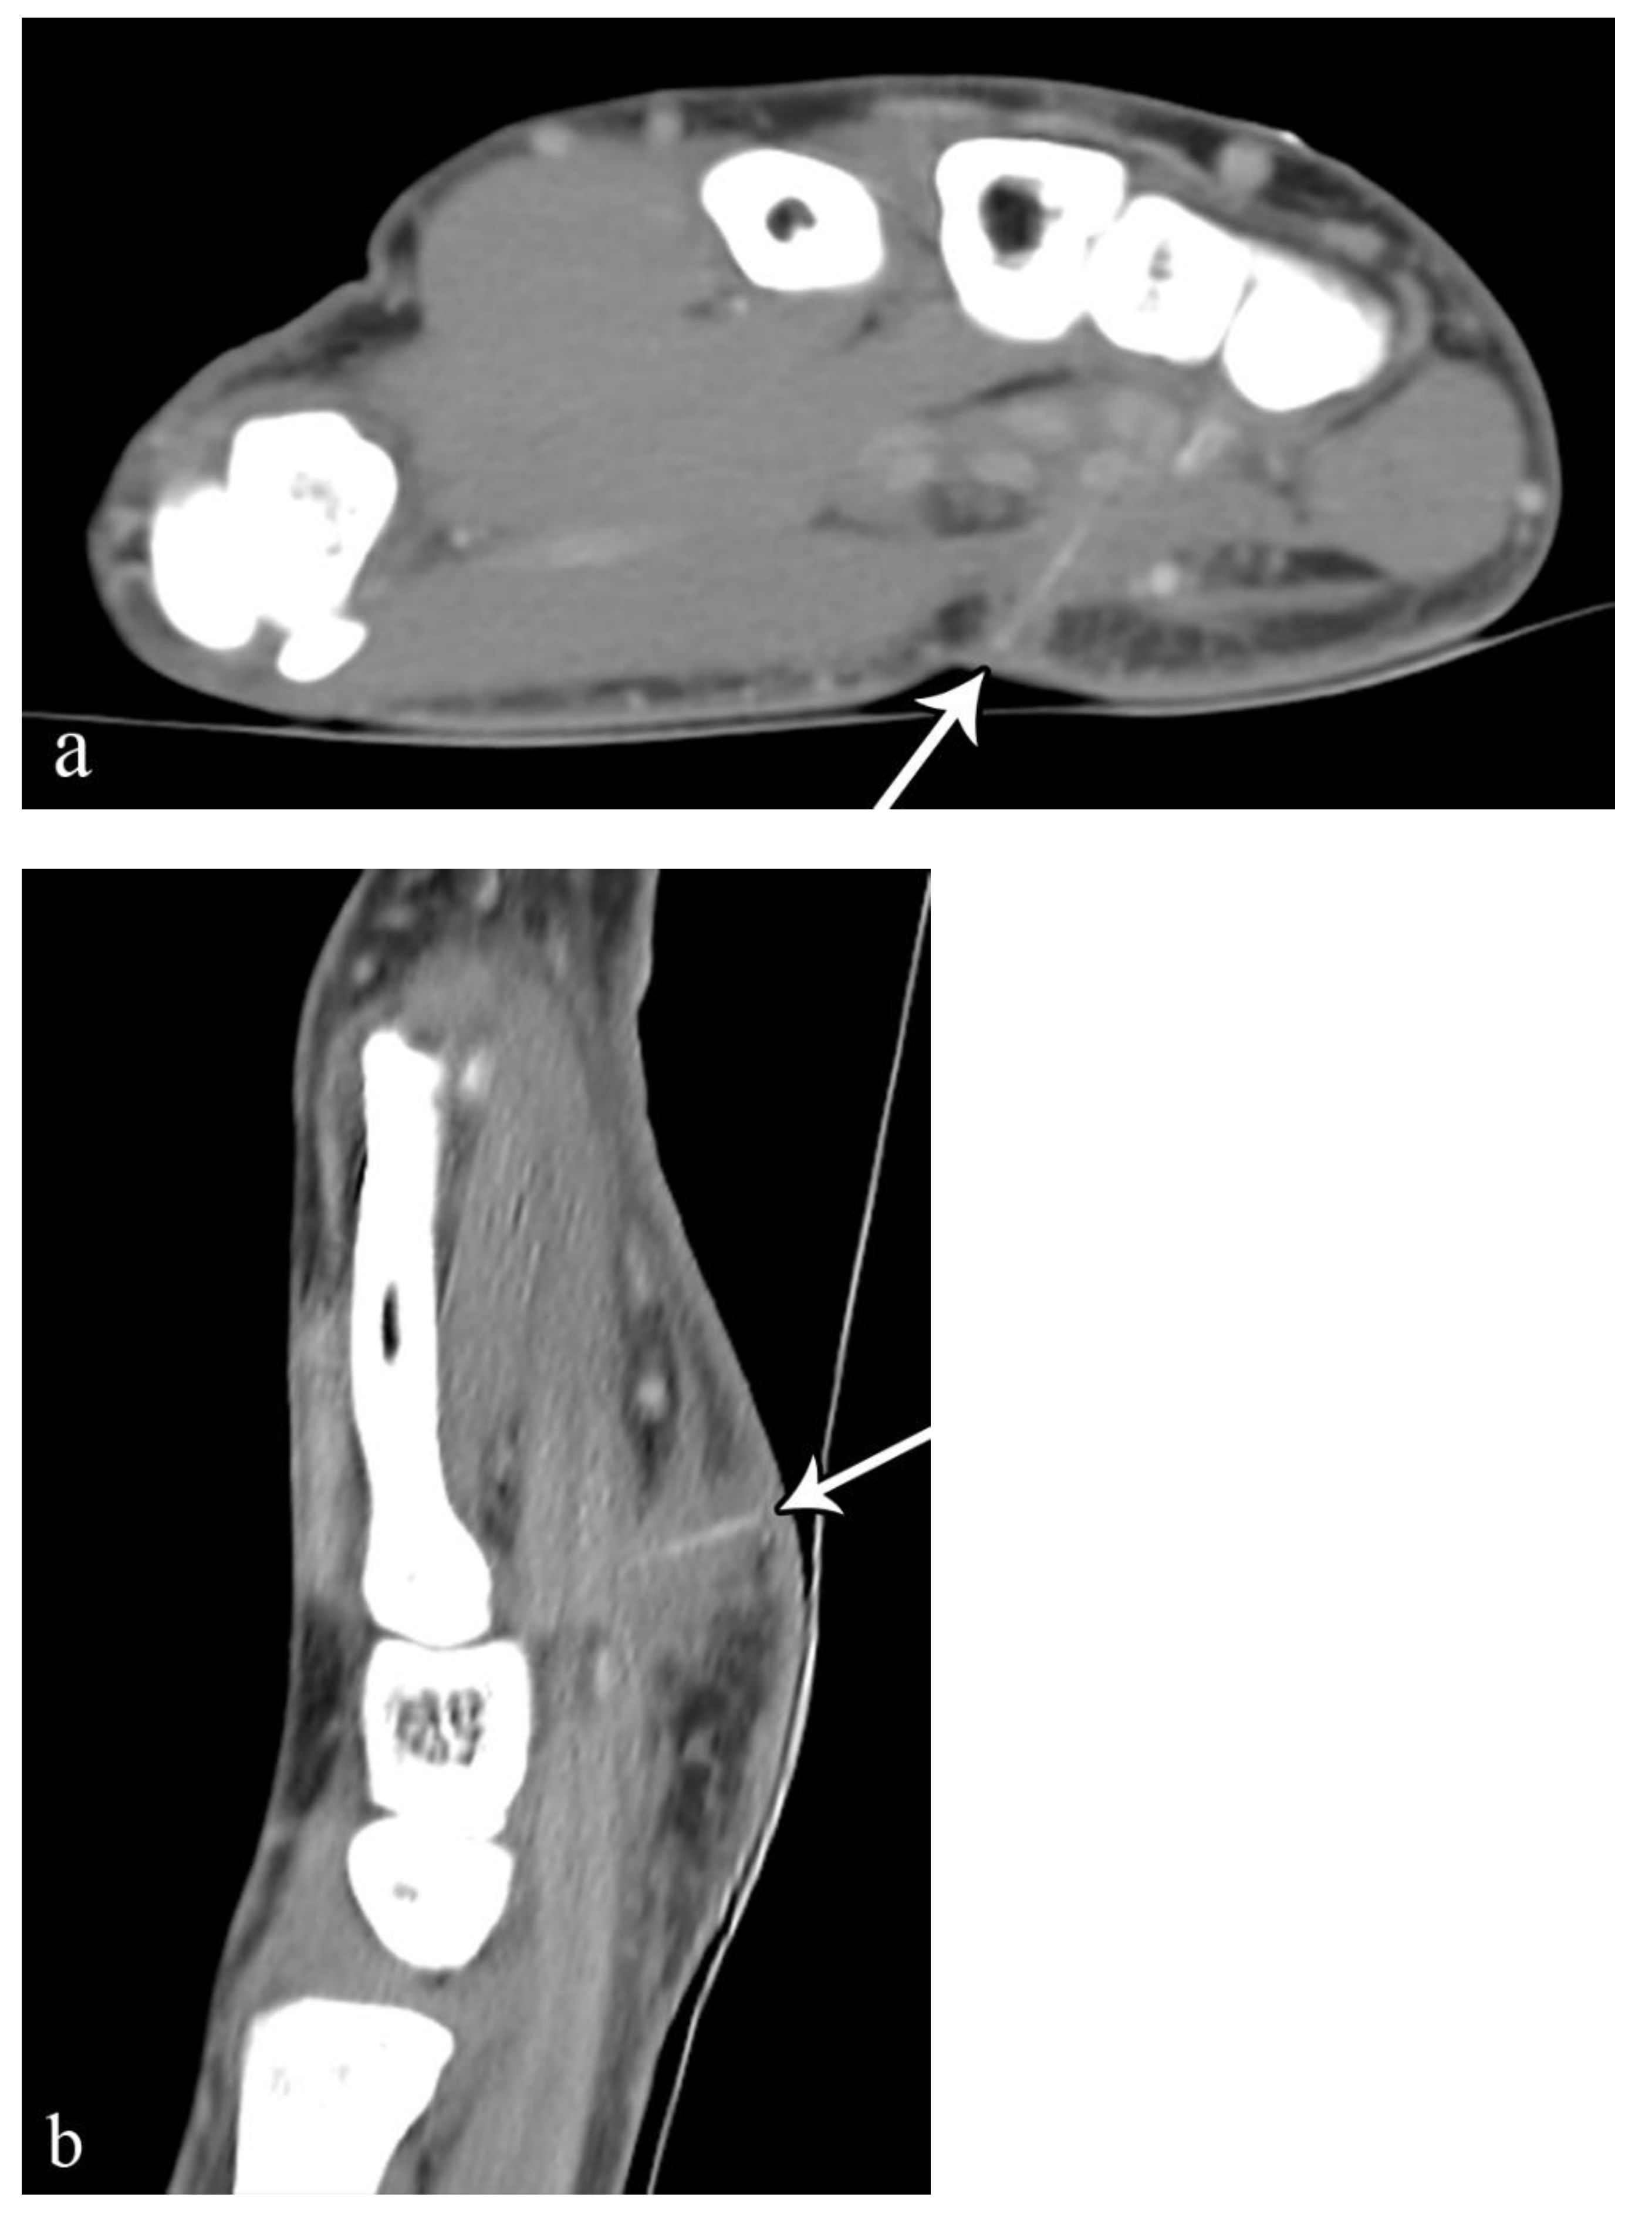

2.3. Soft-Tissue Foreign Body